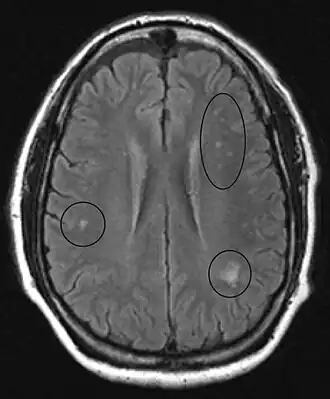

MRI image of the brain in vitamin B12 deficiency, axial view showing the "precontrast FLAIR image": note the abnormal lesions (circled) in the periventricular area suggesting white matter pathology.

MRI of the brain may show periventricular white matter abnormalities. MRI of the spinal cord may show linear hyperintensity in the posterior portion of the cervical tract of the spinal cord, with selective involvement of the posterior columns.